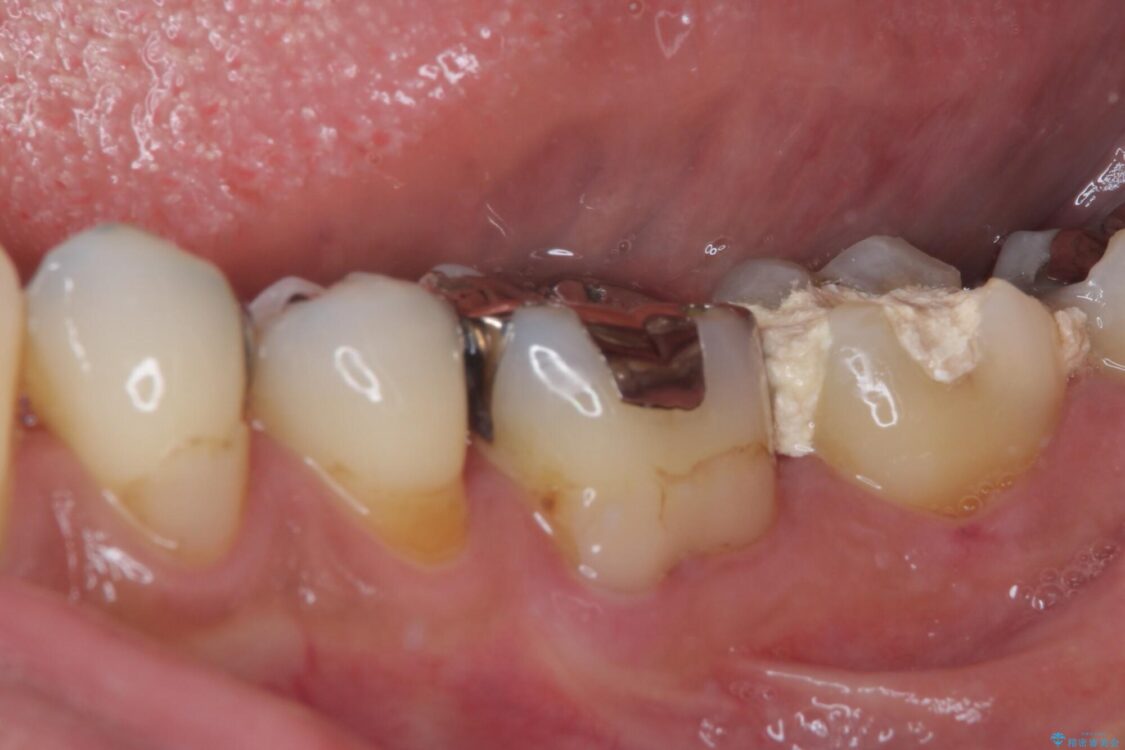

• 治療をしても違和感の続く奥歯 神経を極力残した虫歯治療 治療前画像